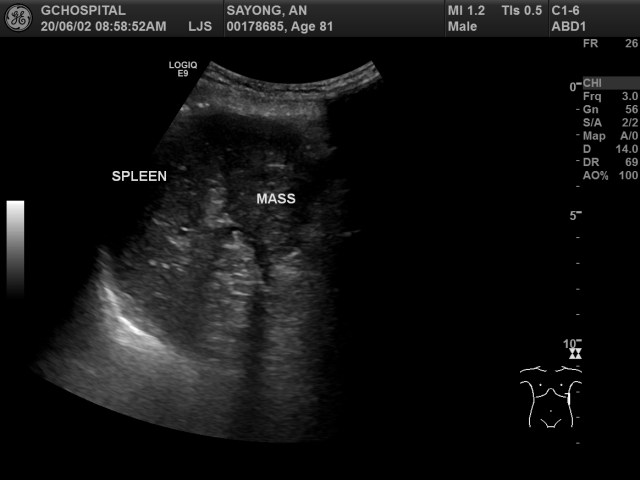

이번에는 탐촉자를 왼쪽 옆구리쪽에 대어서 비장 근처를 확인해보았습니다. splenic hilum 근처에 위치한 종괴와, 바로 밑에 연결되있는 췌장 꼬리를 확인할 수 있습니다. CT에서는 확실하게 구분되지 않았던 비장과 종괴 사이의 경계는 비교적 뚜렷하게 구분이 되어있고, 췌장 꼬리부위와 종괴가 전혀 구분되지 않은 것을 확인할 수 있습니다. 해당 종괴는 췌장 꼬리부위에서 발생한 악성종양으로 보입니다.